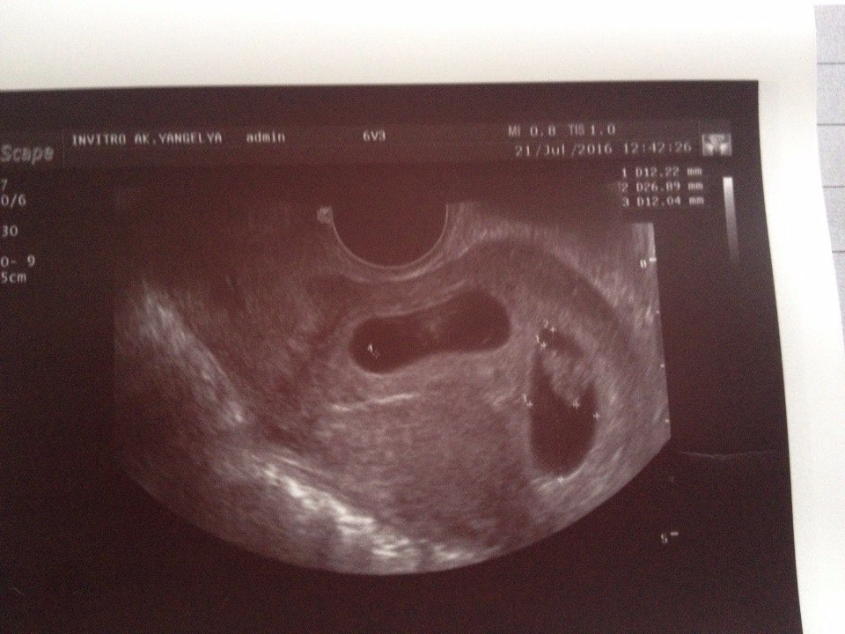

Двойни На Ранних Сроках Беременности

Фото Узи Двойни На Ранних Сроках Беременности 144 фото